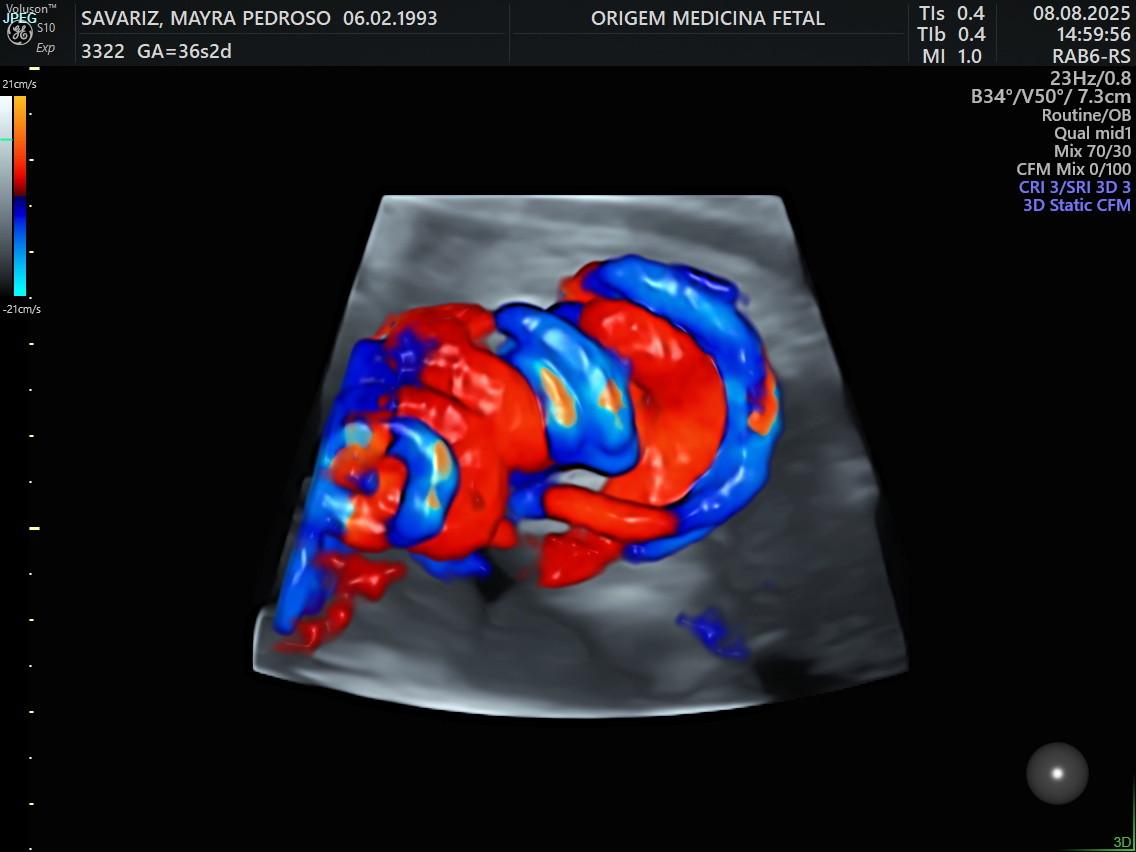

- Ultrassom Obstétrico com Doppler

- Ecocardiografia Fetal